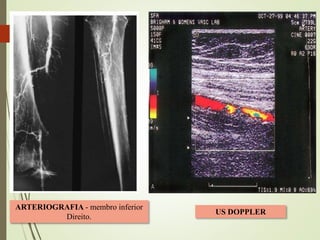

ARTERIOGRAFIA - membro inferior

US DOPPLER

 DIAGNÓSTICO COMPLEMENTAR Nãoinvasivo: - Doppler = severidade da isquemia, a localização da oclusão, causa, se há presença de doença aterosclerótica no mesmo lado e contralateral, se há circulação colateral. - Angioressonância magnética , tomografia helicoidal Invasivo: - Arteriografia = aspecto da oclusão, visualiza aspecto dos vasos distais, aspecto da circulação colateral, define o prognóstico sobre a possibilidade de restauração arterial. NÃO DEVE RETARDAR A TERAPÊUTICA!! DIAGNÓSTICO